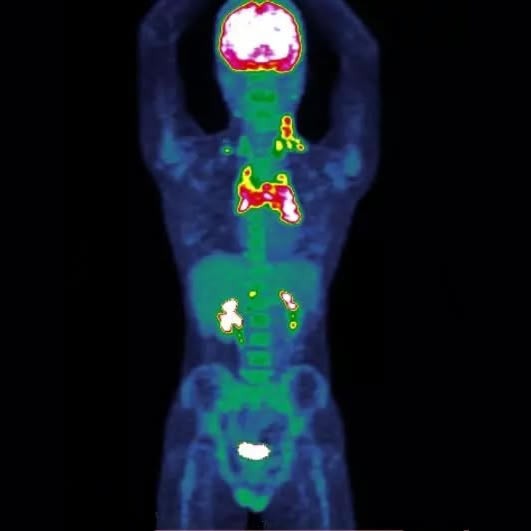

A medicina nuclear é uma especialidade médica que utiliza pequenas quantidades de substâncias radioativas para diagnosticar diversas doenças. Por meio desses exames, é possível obter imagens funcionais de órgãos e tecidos, permitindo uma análise precisa do funcionamento do corpo.